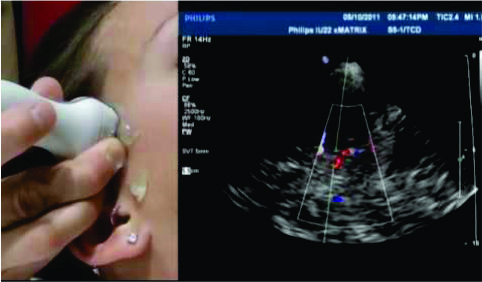

2D ECHO

2D Echocardiography, a non-invasive imaging technique that provides precise visualization of heart structures and function. With a trained sonographer and advanced equipment, we produce detailed images of the heart in real-time. This diagnostic tool aids in assessing cardiac health, identifying abnormalities, and guiding treatment decisions, ensuring comprehensive cardiovascular care for our patients.